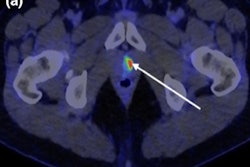

PSMA responders: patient (A) with the disappearance of all PSMA-positive lesions (complete response) and patient (B) with a decrease of PSMA-TV >30% (partial response). PSMA nonresponders: patient (C) with the appearance of new lesions and increased PSMA-TV >30% (progressive disease) and patient (D) with neither new PSMA-positive lesions nor PSMA-TV 30% changes (stable disease). Image courtesy of the Journal of Nuclear Medicine.After a median follow-up of 23 months, a total of 16 deaths had occurred. Among the whole population, responders identified on Ga-68 PSMA-11 PET/CT had longer overall survival compared to those identified as nonresponders (median overall survival not reached versus 12 months, hazard ratio 0.10), the researchers found.